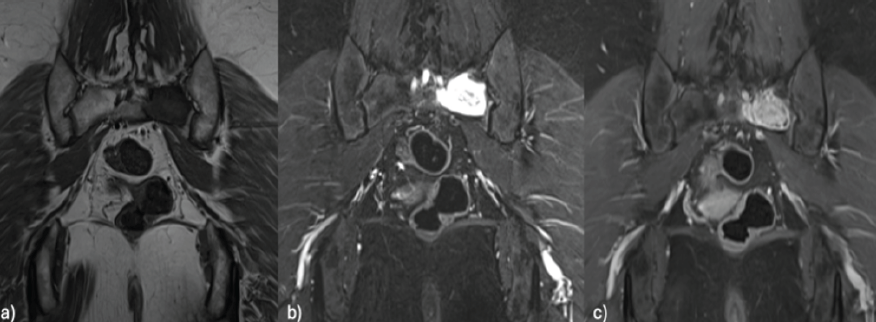

Magnetic resonance imaging (MRI) demonstrated a predominantly T2 hyperintense (Fig. 3) and T1 hypointense lesion with calcifications and progressive enhancement in delayed phases. The image showed no signs of diffusion restriction or sacroiliac infiltration.

Figure 3: Magnetic resonance imaging coronal view: Hypointense lesion on T1 (a), hyperintense on short tau inversion recovery (b), and contrast enhancement on gadolinium-enhanced T1(c).